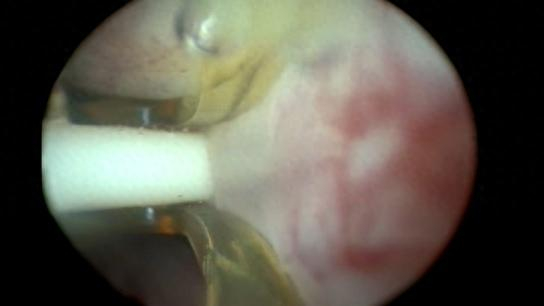

Rezūm手术是如何进行的?

1、在插入一次性使用热蒸汽治疗器械之前,会在患者体外进行一次治疗前水蒸气循环治疗

2、热蒸汽治疗器械插入患者尿道并评估前列腺的状况

3、持续释放9秒高温水蒸汽治疗